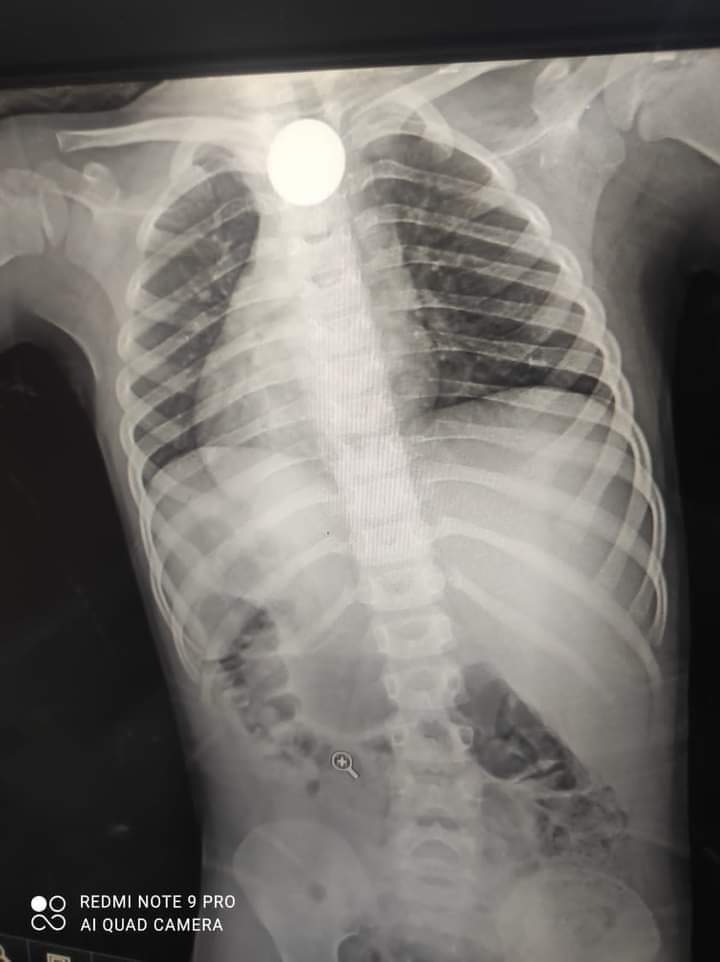

فريق طبي بمستشفي دكرنس بالدقهلية يستخرج عملة معدنية ابتلعتها طفلة

نجح فريق طبي بمستشفي دكرنس العام بمحافظة الدقهلية في استخراج عملة معدنية ابتلعتها طفلة عمرها أربع سنوات.

ومن جانبه أكد الدكتور شريف مكين وكيل وزارة الصحة بمحافظة الدقهلية أن مجموعة متميزة من الفريق الطبي داخل مستشفى دكرنس نجح في استخراج عملة معدنية ابتلعتها طفلة تبلغ من العمر أربع سنوات.